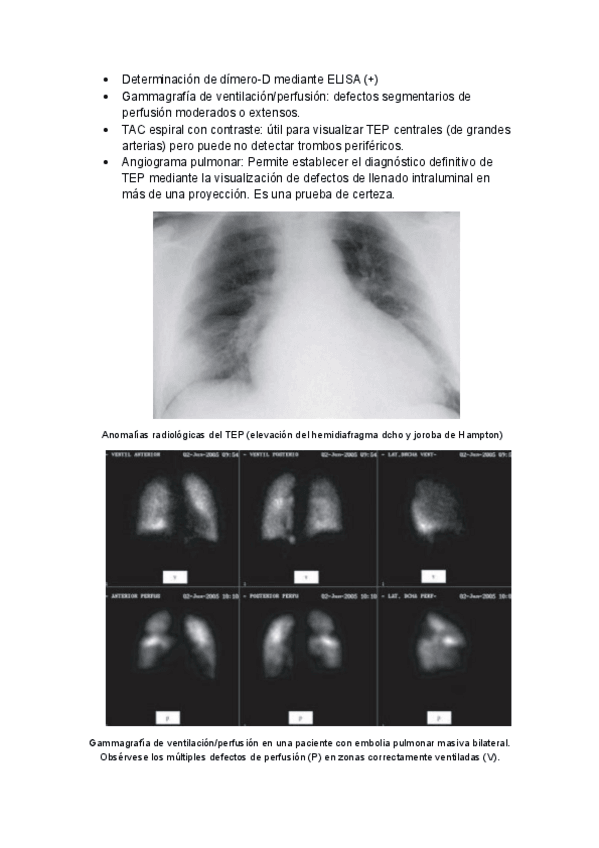

He publicado nuevos apuntes de 2º Enfermería en alteraciones de la salud I: TROMBOEMBOLISMO-PULMONAR.pdf

4 páginas